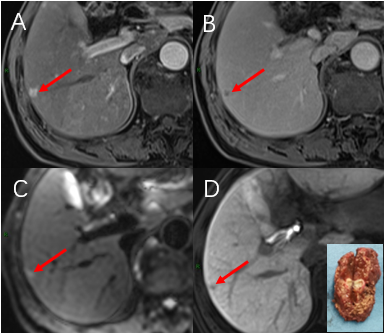

近年来,影像医学飞速发展,各种影像检查新技术层出不穷,这些新技术对临床医师诊断疾病有极大的帮助,患者也从中获益良多。 但是临床医师经常遇到这样的困惑,“这个病人/这种疾病适合哪种影像检查?”患者也常常有这样的疑问,“为什么医生要让我做这个检查?到底有没有必要?” 针对这类问题,仁济医院放射科将陆续推出一系列关于影像新技术的科普文章,期望能为广大医务工作者和患者答疑解惑,更好推动诊疗水平的提高及各类影像学新技术的运用。 李先生30岁出头,患有乙肝后肝硬化多年,今年医生让他做“肝细胞特异性对比剂磁共振增强检查”进行体检,发现肝内有一枚直径仅8毫米左右的结节,考虑为微小肝癌。 随后医生为他进行了肿瘤切除手术,病理显示为:早期的微小肝癌。由于肿瘤发现早、治疗及时,李先生术后恢复良好。 这是一种针对肝脏肿瘤的磁共振检查,检查时需要静脉内注射肝细胞特异性对比剂:钆塞酸二钠(Gd-EOB-DTPA)。 钆塞酸二钠除了具有与传统磁共振细胞外对比剂相似的功能以外,还可以通过肝细胞膜上的OATP通道转运进入肝细胞,再通过MRP通道排泄入胆道。钆塞酸二钠在肝细胞内的停留使得整个肝脏明显强化,在静脉注射后20-60分钟左右达到峰值——这段时间称为肝胆期。 2020年,全球肝癌新发病例约90万例,其中中国占了45.3%,全球肝癌死亡病例约83万例,中国占47.1%。肝癌是我国导致死亡的第2大癌症,导致如此高死亡率的最重要原因在于,我国肝癌患者超过七成为中晚期。因此,对肝癌高危人群定期进行体检,早期发现肿瘤意义重大。 肝癌高危人群通常指的是各种类型引起的慢性肝炎(特别是慢性病毒性肝炎)、肝硬化、以及既往有过肝癌病史的患者。由于肝癌大多遵循从再生结节-不典型增生结节-分化良好肝癌-分化不良肝癌的自然演变过程,监测、区分上述这些不同类型病变的性质就变得十分重要。 还记得前面提到钆塞酸二钠是通过肝细胞膜上的OATP通道转运吗?肝硬化结节从良性逐渐发展成为肝癌的过程中,伴随着正常肝细胞功能的丧失和OATP通道的逐渐减少。肝胆期病灶灰度也会表现出与周围灰白色背景明显差异的灰黑色,从而可以通过肝胆期结节在图像上灰白程度帮助判断是否已经进展到肝癌。由于肝胆期正常肝脏背景会变白,可以非常敏感的检出灰黑色的小病灶。就像在白纸上有一粒黑色的芝麻,尽管芝麻很小,但也很容易被发现。 ▲ 一例1.2cm小肝癌患者。肝细胞特异性对比剂磁共振增强检查(A)动脉期和(B)门脉期常规图像上的病灶十分隐匿。(C)20分钟肝胆期白色背景下病灶明显(红箭),灰黑色的病灶提示该结节已经进展到肝细胞癌阶段,丧失了OATP通道表达。(D)为手术的病灶剖面,病理为肝细胞癌。 ▲ 一例仅6mm的微小肝癌。肝细胞特异性对比剂磁共振增强检查(A)动脉期和(B)门脉期表现为典型“快进快出”强化方式的微小病灶(红箭)。(C)DWI弥散加权图像上轻微弥散受限。(D)20分钟肝胆期图像上结节呈灰黑色,考虑肝癌可能性非常大。右下角为手术标本剖面,病理结果为肝细胞癌。 怀疑局灶性结节增生的患者 对于非肝癌高危人群来说,肝细胞特异性对比剂磁共振增强检查主要用于判断肝内结节是否是局灶性结节增生(FNH,Focal Nodular Hyperplasia)。FNH是第二常见的肝脏良性肿瘤,由于FNH内含有正常肝细胞,因此在肝胆期上通常表现为同背景相似的灰白色,而其他类型肿瘤不含有正常肝细胞在肝胆期表现为灰黑色,从而可以进行鉴别。 有原发肿瘤病史怀疑肝脏转移瘤的人群 由于肝胆期正常肝脏强化较门静脉期更为显著,很容易发现在“白色”背景下的“黑色”小病灶。对于有原发肿瘤病史怀疑存在肝脏转移瘤的患者,肝细胞特异性对比剂磁共振增强检查可以帮助发现潜在的肿瘤微小转移灶。 检查报告结论有点复杂,啥意思呀? 对于有肝癌危险因素的患者,我们使用LI-RADS v2018版报告规范对病变进行分级。 LR-M = 高度怀疑/几乎肯定肝脏恶性肿瘤 LR-TIV = 肝脏恶性肿瘤合并静脉癌栓 LR-5 = 几乎肯定肝细胞肝癌 LR-4 = 很有可能肝细胞肝癌 LR-3 = 对于该病灶不能确定良恶性 LR-2 = 很有可能是良性病灶 LR-1 = 几乎肯定是良性病灶 LR-NC = 因技术或其他原因对病灶性质归类 对于肝脏肿瘤局部治疗后,如射频消融、经皮无水乙醇消融、冷冻消融、微波消融、动脉栓塞或化疗栓塞等的治疗反应评估,将使用以下分级(TR表示治疗反应Treatment response): LR-TR Viable = 治疗后存在活性肿瘤 LR-TR Nonviable = 治疗后无活性肿瘤 LR-TR Equivocal = 治疗后肿瘤活性不确定临床故事